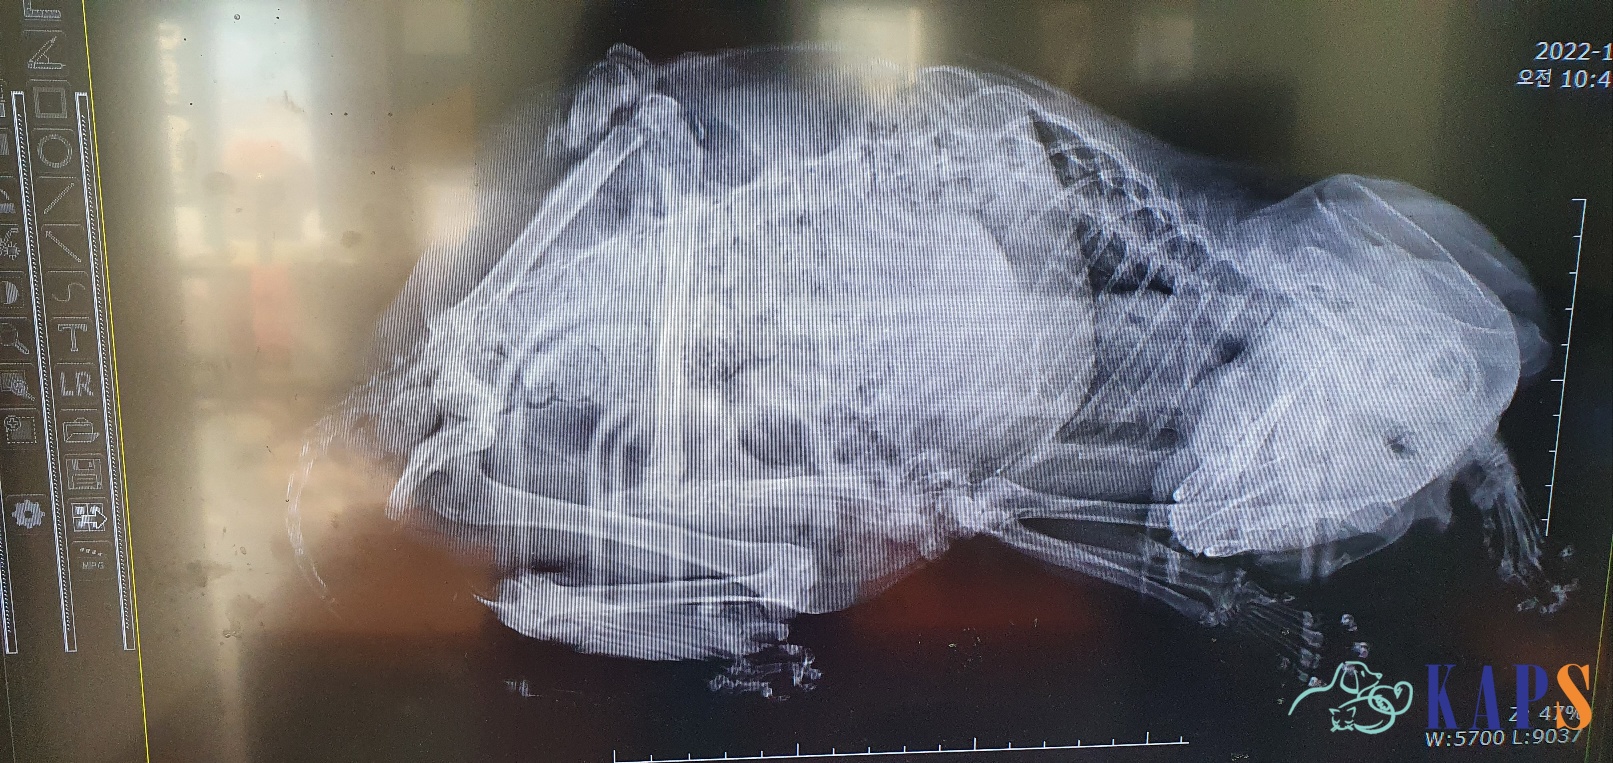

마취 없이 이동장채로 찍은 X-ray

그리고 안경이의 다리는 예상대로 골절.

하지만 단순 골절이라 치료는 비교적 쉬웠습니다.